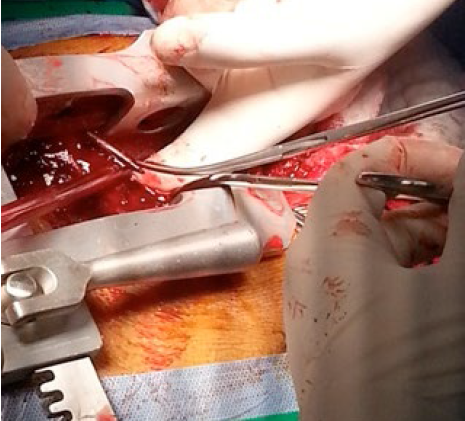

图4:术中可见心脏没有被钉子穿透受损的痕迹

患者,25岁,男性。在进行装修作业时意外将钢钉射入体内被紧急送往急诊科治疗。临床检查,患者意识清醒,血压80/50mmHg,心率120 次/分,胸部左侧锁骨中线第二肋间有一个约2cm大小的开放性创伤。胸部X线显示一颗钉子与心影重叠。经胸超声心动图显示约1cm心包积液。胸部CT显示钉子处于胸骨后且钉子头部指向右心室,患者被紧急送往手术室。术中发现钉子头部已经穿透心包表面,未伤及心脏,医生顺利将其取出,术后患者病情平稳,7天后顺利出院。